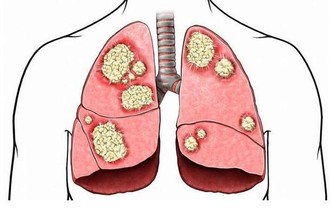

風寒感冒。熱敷大椎穴有利於祛除體內寒氣,解表發汗,以達到治療風寒感冒的目的。大椎穴位於頸後正中線上,第七頸椎棘突下凹陷處,屬於督脈穴位。督脈統領一身的陽氣,為陽脈之海。熱敷時以感覺微微發燙為宜,最好是晚上睡覺前進行,一般熱敷20分鐘左右。對於感冒伴有咳嗽者,可加肺俞(第三胸椎棘突下,左右旁開兩橫指)、定喘(大椎穴左右旁開半橫指)等穴位。熱敷後要注意保暖,以免寒氣入侵。